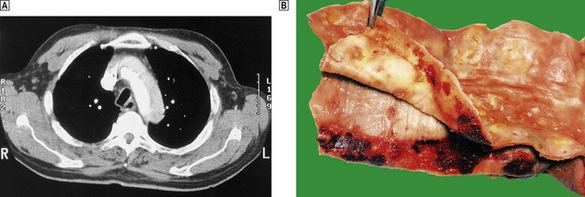

Aortic dissection (dissecting aneurysms)

In aortic dissection, blood is forced through a tear in the aortic intima to create a blood-filled space in the aortic media (Fig. 13.9). This can track back into the pericardial cavity, causing a fatal haemopericardium, or can rupture through the aortic adventitia. In occasional cases the track re-enters the main lumen to create a ‘double-barrelled’ aorta. The intimal tear and the anatomical features of the aorta can be demonstrated in life by CT or MRI scanning. The underlying pathology is poorly understood. In some, but by no means all, cases there is pronounced degeneration of the aortic media. This is the so-called cystic medial necrosis and is characterised by mucoid degeneration and elastic fibre fragmentation. An exaggerated form of this change is seen in Marfan’s syndrome, a congenital disorder of the expression of a glycoprotein, fibrillin, closely associated with elastin fibres. The strongest risk factor for dissecting aneurysm is systemic hypertension. In some cases the intimal ‘entry’ tears are around atheromatous plaques, but in most cases they involve disease-free parts of the aorta. Without treatment, the mortality from dissecting aneurysm is at least 50% at 48 hours, and 90% within 1 week. The immediate aim of treatment is to contain the propagating haematoma by reducing arterial pressure. Surgical repair is feasible in some patients, especially if the process affects the proximal aorta.

image

Fig. 13.9 Aortic dissection. image A CT scan of a patient with an acute dissection of the ascending aorta. There are two patterns of contrast enhancement in the aorta. The whiter is the main lumen and the greyer the false lumen. image The innermost portion of the aortic wall has been peeled away to reveal the underlying haemorrhagic tract.